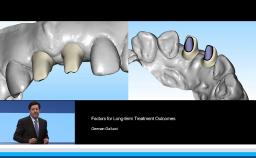

German Gallucci

Boston, United States